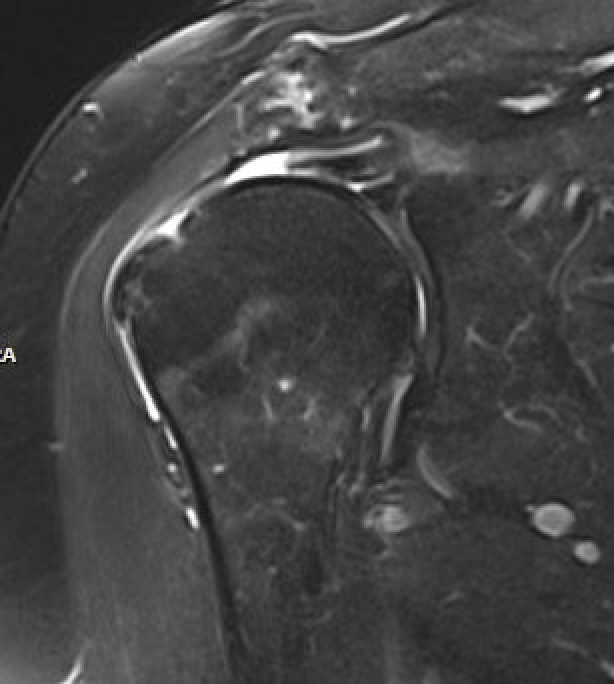

MRI

Look for

- supraspinatus / infraspinatus / subscapularis / long head of biceps pathology

- partial verus full thickness

- size of tear in coronal and sagittal planes

- retraction

- atrophy / fatty infiltration

Full thickness rotator cuff tears

Small full thickness rotator cuff tear of supraspinatus - retracted to footprint

Large full thickness tear of supraspinatus and infraspinatus tendon - retracted to midhumeral head

Massive rotator cuff tear of the supraspinatus and infraspinatus tendon - retracted to glenoid